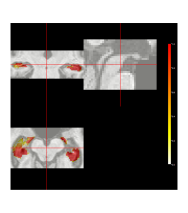

As already mentioned, only healthy brains are used as atlases. The systematic differences are not completely captured by atlas-target image dissimilarities. Despite accounting for image dissimilarity, there is a tendency for the established methods to over-segment the hippocampus. The Bayesian label fusion model facilitates explicit incorporation of the estimated gray matter pattern as a predictor. Our prior specification allows for the possibility that the tissue classes are incorrectly assigned in some places, but are mostly reliable. The effect of the gray matter segmentation as auxiliary information can be clearly seen by comparing it even with our own model in which this information is ignored but the model is otherwise identical. Figure 10 displays the posterior inclusion probabilities obtained without using the gray matter information, along with the results already presented for reference. Using only the intensity-similarity-weighted distance labels yields a Bayesian regression analogue to the other approaches that only weight by intensity similarity. The additional tissue class information is able to prevent oversegmentation of the diseased structure.

In practice, an anatomical structure is segmented to obtain important information such as its volume or average image intensity within the structure. In our case, segmenting the hippocampus is a step toward estimating its volume. If we only obtain a binary map, then the only way to estimate the volume is by summing the indicators. Doing so ignores many sources of uncertainty, including image pre-processing, registration error, biological variation, and rater variability. Monte Carlo sampling also facilitates estimation of a distribution of plausible volumes through , defined in Section 3. Figure 11 displays the marginal volume densities for the diseased brain of interest, both with and without gray matter included in the Bayesian label fusion model. Vertical lines indicate the manually-segmented volume and the volume estimates from the other procedures considered. The benefit of including the gray matter information is again evident with the improved agreement of the volume distribution with the manual segmentation. In this case, though, we see that even without the gray matter information the Bayesian model outperforms the three majority voting procedures.